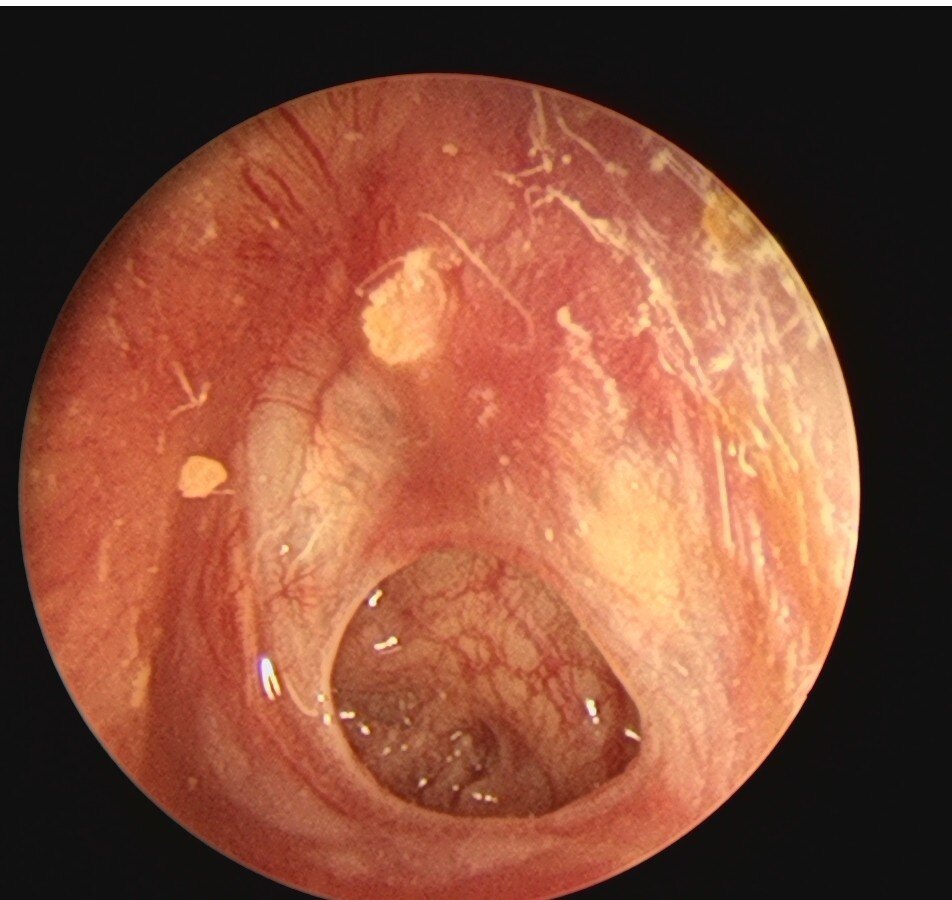

When you have a cold, it’s most uncomfortable to have a blocked nose. Many people will blow their nose hard with both nostrils to feel relieved. But this method is actually wrong! For children, the nasal cavity and ears are connected, and blowing their nose forcefully can “press” bacterial mucus into their ears, which can easily lead to otitis media, causing pain and affecting hearing. For elderly people with hypertension, suddenly blowing their nose forcefully can cause a sudden increase in blood pressure, which is very dangerous.

The correct way to blow your nose is actually very simple: take a soft tissue, gently press one nostril first, and then use the other nostril to blow your nose out gently, without using too much force. Blow one side before switching to the other. Finally, remember to wash your hands.

What should I do if my nose is blocked and I can’t sleep? You can try these non medicated methods: pour a cup of hot water and inhale warm steam through your nose (be careful not to burn it); Alternatively, you can use physiological saline nasal spray to moisten the nasal cavity and dilute nasal mucus, which can be used by both children and the elderly; When sleeping, raise the pillow a little higher and sleep on your side, so that your nose can breathe better.